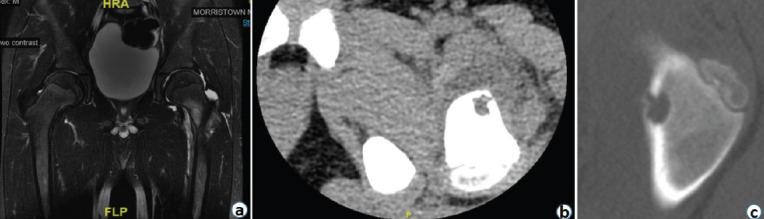

A 7-year-old male presented with complaints of hip pain and inability to bear weight. X-rays revealed Brodie's abscess in the proximal femur which was initially misdiagnosed as toxic synovitis with an incidental unicameral bone cyst (UBC).